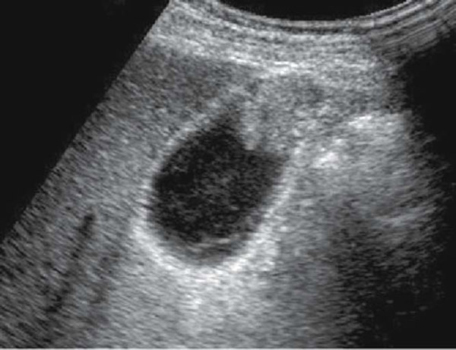

Epaissisement de la

paroi vesiculaire > 3mm , la contenue est irregulie

et image de calcul de infundibulum vesiculaire

. Cholecystite aigue lithiasique |